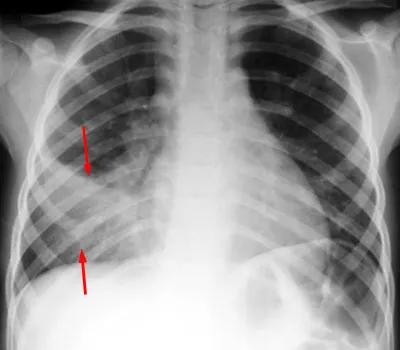

Diagnosis: Primarily clinical. Chest X-ray is not routinely recommended but may show hyperinflation, peribronchial thickening, and atelectasis.